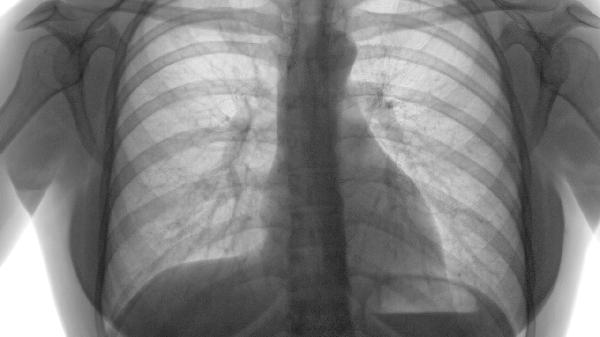

发生肺气肿应该注意什么 发生肺气肿需注意四个事项

发生肺气肿需注意戒烟、预防呼吸道感染、规范氧疗、适度运动等事项。肺气肿是慢性阻塞性肺疾病的常见表现,与长期吸烟、空气污染等因素相关,患者需通过综合管理延缓病情进展。